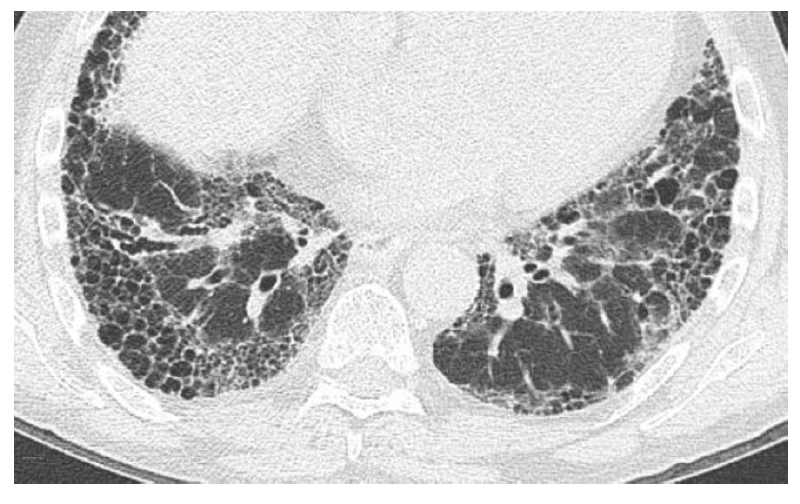

What is this? (what feature is shown?)

UIP (honeycombing?)